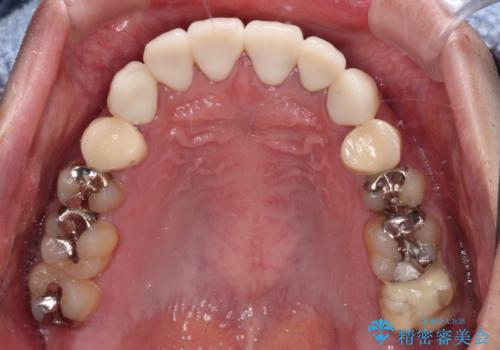

全顎的にむし歯が多く、治療が必要な歯はたくさんありましたが、まずは非常に目立つ前歯から処置を行うこととしました。

むし歯は歯肉内にまで進行していると外科処置が必要となりますが、ギリギリの位置でとどまっていたため、速やかにオールセラミッククラウンにて補綴治療することとしました。